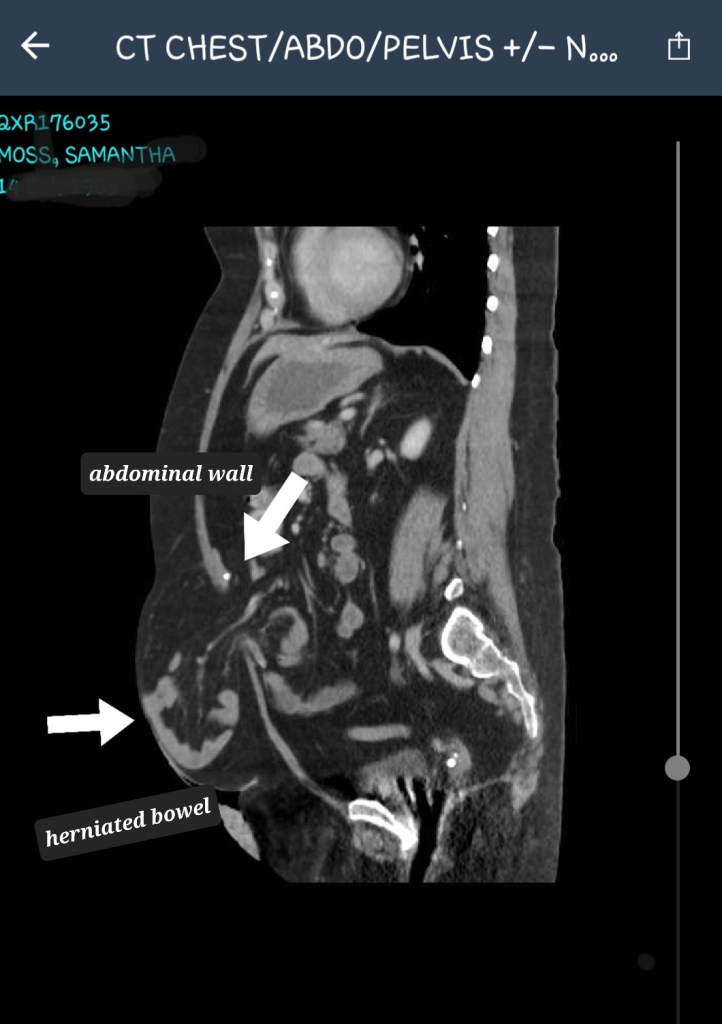

I so wish my body would stop disrupting my life. I wish it would stabilise for years rather than months. Instead, it has a relapsing remitting type of disease. A disease, no one ever really knows what name to give it. It’s actually a collection of diseases. It threatens to be cancer and is deemed to be malignant in nature, but my blood tests and scans etc, show something low grade despite severe damage to bones and organs. So an idiopathic disease is the diagnosis, although it’s made up of rheumatoid arthritis, Sjogren’s disease, non Hodgkin’s Lymphoma, osteopetrosis (rare bone disease), osteoporosis, trigeminal neuralgia, bowel prolapse, severe abdominal wall separation, adhesions disease, an unstable spine and I know I’m missing others from this list.

So you can imagine how I felt when confronted with the news my abdominal wall separation was now five cms, in the severe category, and had increased by three cms in two months!! Just crazy. I knew my latest CT scan would show something like this, especially considering I literally look eight months pregnant. However, even I found the scan images confronting, despite all I’ve been through.

Oh for heaven sake Sam, that hernia looks awful. Ouch. That just looks awful I am so sorry this is happening. Sheryl and I will be in prayerful requests for the very best outcome.

Thanks Rick. Not the best is it and I could have done without an extra complication but we’ll get it sorted as soon as possible. I have 6 medical appointments next week so someone will come up with a plan 🤔🙄☺️